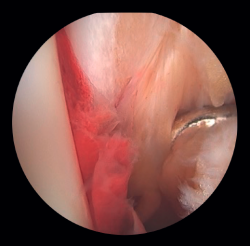

Si la lesión del deltoideo compromete solo a la parte anterior, podremos realizar la reinserción de forma artroscópica mediante implantes reabsorbibles. Si la desinserción del deltoideo es completa, preferimos realizar la reinserción de forma abierta por la dificultad que entraña colocar los implantes en la zona posterior del maléolo y el riesgo de lesión neurovascular (Figura 5).

Figura 6. A: lesión de sindesmosis; B: control de la reducción para evitar la sobrecorrección; C: control intraoperatorio de la correcta reducción del peroné en la incisura.